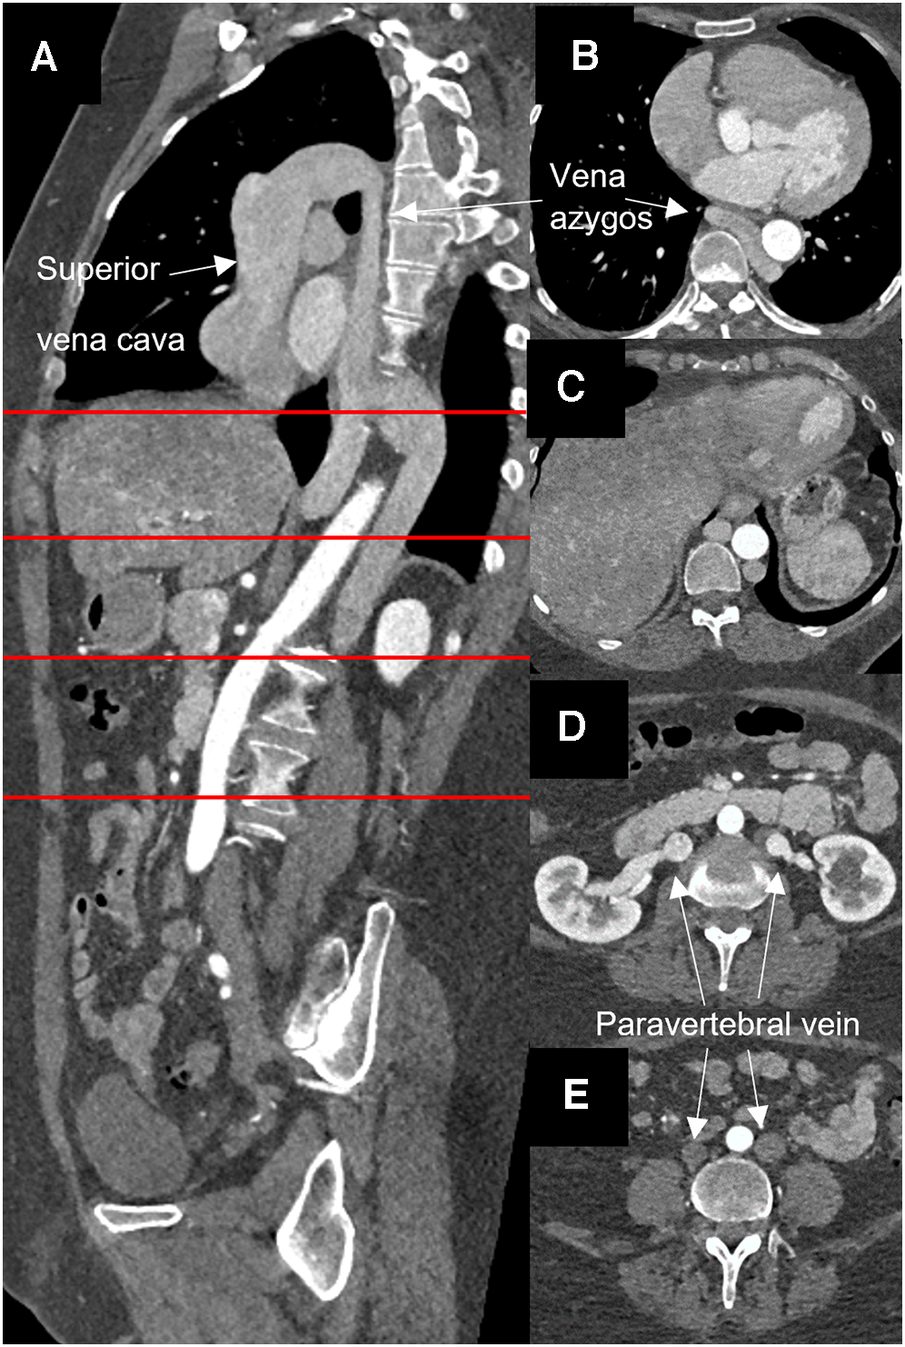

A 54-year-old woman presented with severe aortic valve stenosis and an ascending aortic aneurysm. Echocardiography revealed a maximum gradient across the aortic valve of 58 mmHg, a calculated valve opening area of 0.7 cm2, a bicuspid valve morphology, and ventricular hypertrophy. Left ventricular function was normal. CT angiography confirmed an aneurysm of the ascending aorta of 46 × 45 mm. Additionally, an azygos continuity with complete agenesis of the inferior vena cava was found incidentally in routine CT angiography. Both iliac veins were found to directly drain into the corresponding paravertebral vein and then merged with the left and right renal veins to form a large azygos vein (Figure 1).

Figure 1

Computed angiopgraphy showing atresia of the inferior vena cava and azygos continuity. (A) Sagital layer, (B–E) horizontal layer at the sites marked in red.